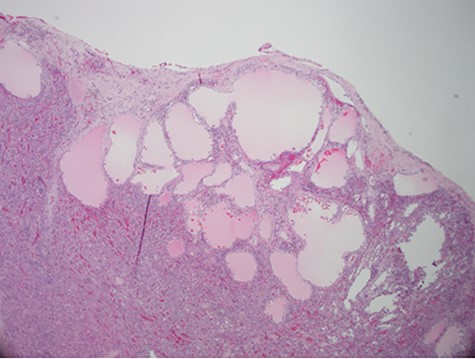

Despite aggressive resuscitation, the patient’s hemodynamics and clinical exam declined. He was taken emergently to the operating room for exploratory laparotomy, evacuation of hemoperitoneum and splenectomy. The spleen was noted to have an isolated nodular, cystic appearing portion in addition to large area of capsular tear. In total, he received four units of PRBC, four units of fresh frozen plasma and one unit of platelets peri-operatively; however, he continued to show signs of hemorrhagic shock. Morning lab-work revealed a Hgb of 5.9 mg/dL from 7.6 mg/dL despite two additional units of PRBC on post-operative day one. Due to continued decline in Hgb and ongoing tachycardia, he returned to the operating room on post-operative days two and four for repeat exploration. Each procedure failed to identify an obvious source of bleeding, except for diffuse oozing in the peritoneal cavity. Further family discussion revealed a history of Hemophilia A in the patient’s brother, diagnosed during childhood. New diagnostic workup was obtained and was consistent with a variant of Hemophilia A. He was subsequently treated with recombinant Factor VIII to a goal of 80–100%, per hematology recommendations, and underwent definitive closure with hemostasis noted on post-operative day six. Pathology report returned as a ruptured spleen with hemorrhage and a subcapsular nodule with dilated lymphovasculature consistent with splenic lymphangioma (Figs 2 and 3).

Hematoxylin and eosin stain photomicrographs from splenectomy consistent with splenic lymphangioma with 40x magnification.